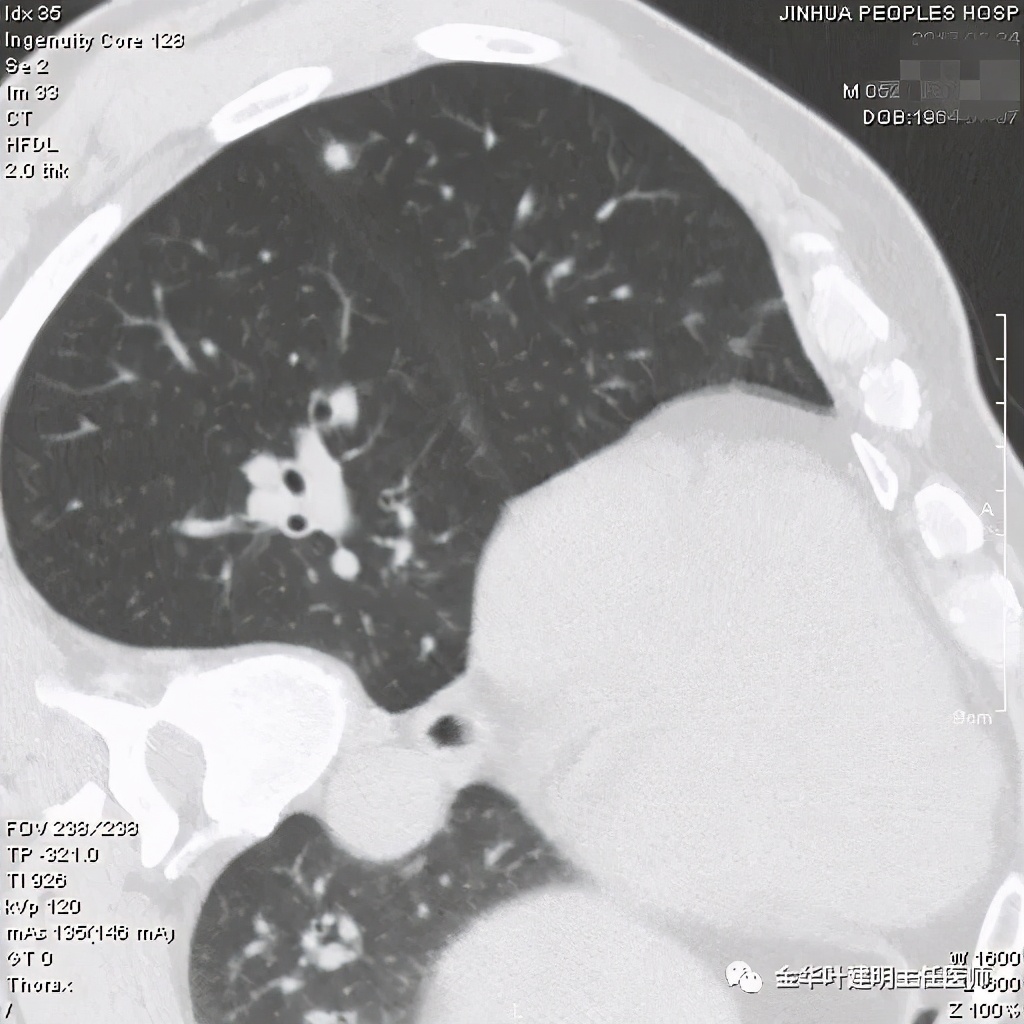

我们来看以往的隐球菌感染是怎样的影像表现:

我们看到它们的共同特征是:实性结节伴有晕征(边缘略糊,看不清的感觉),同时实性的病灶缺乏收缩力(没有胸膜凹陷及毛刺牵拉或纠集感)。